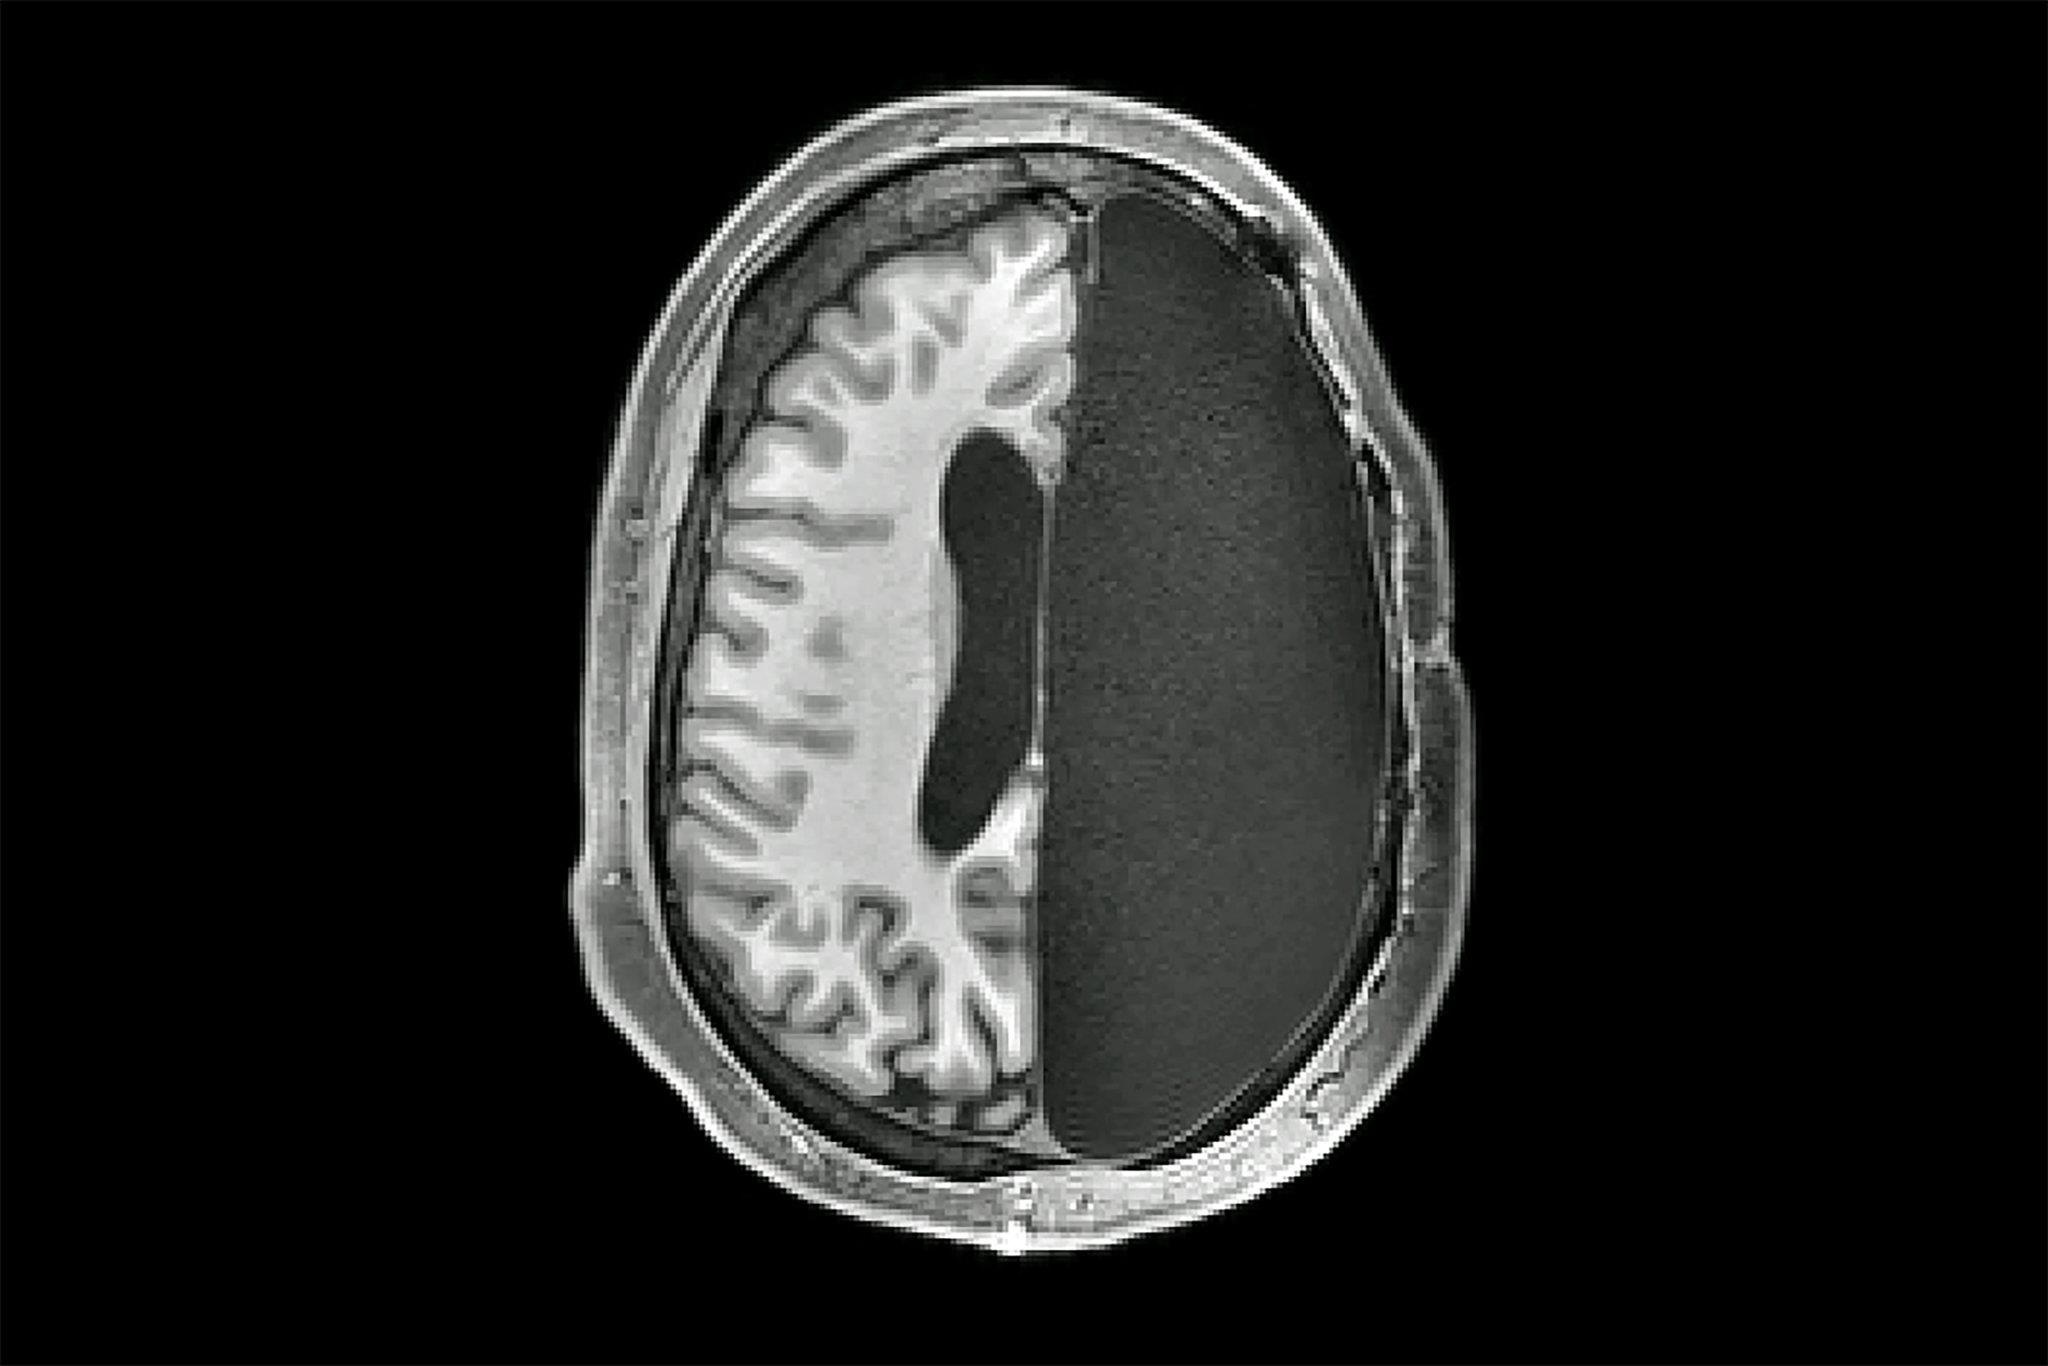

Tổn thương não vĩnh viễn vì ăn mật rắn

Chàng thanh niên 28 tuổi người Trung Quốc mắc động kinh từ 16 năm trước. Bác sĩ phát hiện một phần não bị mất do ký sinh trùng có nguồn gốc từ mật rắn.